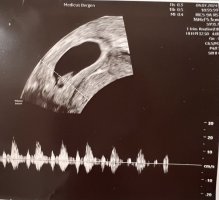

Tok du innvendig eller utvendig?Menstermin og ultralydtermin er begge 6+5. «Perfekt» hjerterytme, «perfekt» størrelsesforhold mellom embryo og plommesekk, ingen blødninger eller forstyrrende «flekker» på bildene og «perfekt» størrelse på embryoet etter «alder». Målt til 8,3 mm. Gynekologen sa at det nå er, basert på funnene, ca. 6% sannsynlighet for abort. Veldig hyggelig besøk hos Medicus før ferien!